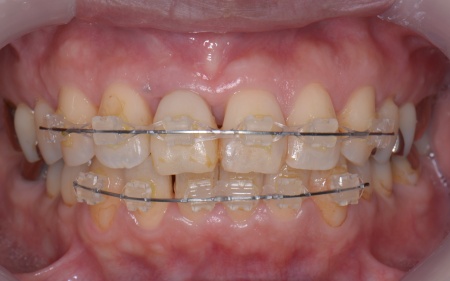

その後、歯の表面に四角いボタン状の装置を接着し、そこにワイヤーを通して歯を動かすマルチブラケット装置による上下前歯の部分矯正を開始します。

歯周組織への負担が軽減できるよう、慎重に力をかけながら段階的に歯を移動させ、徐々に歯並びを整えました。

部分矯正中です。